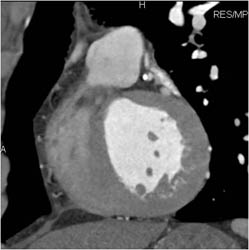

Plaque in LAD